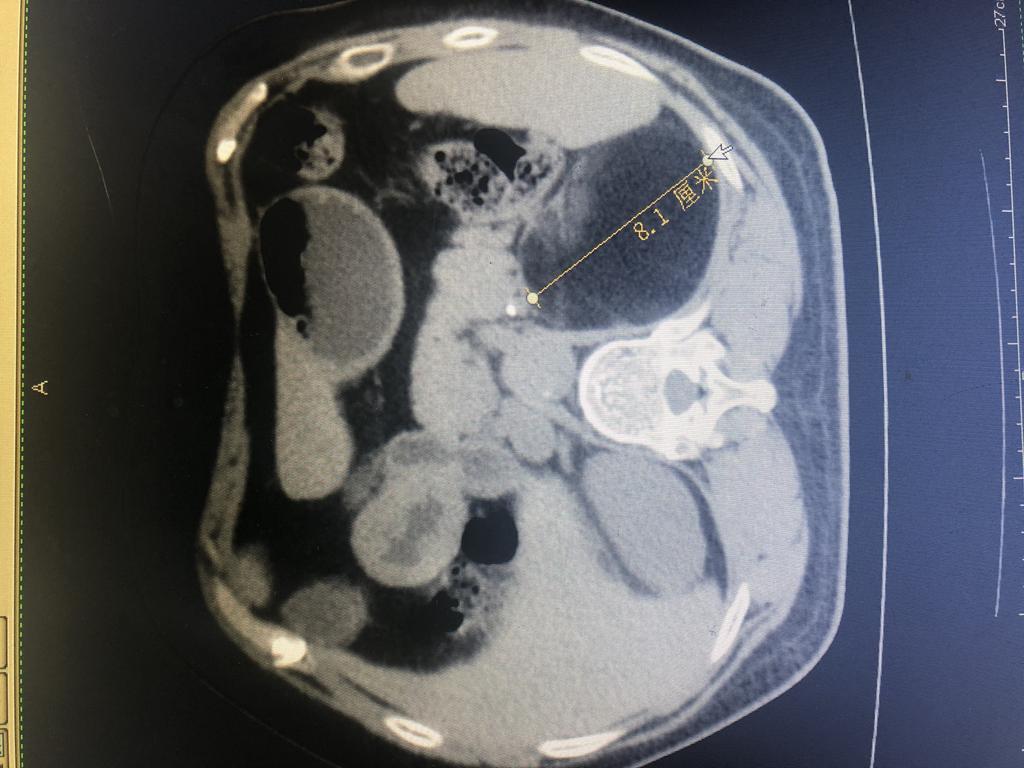

肿瘤CT

患者,女性,61岁,在乡镇医院体检发现左肾上腺有1个8×9cm巨大包块,遂来崇州市人民医院就诊后入泌尿外科住院治疗。因该患者左肾上腺包块大,泌尿外科主任杨华、副主任医师徐浩、医师彭思洋对患者的身体基础情况和病情进行反复评估,决定采取经腹入路行微创手术治疗。